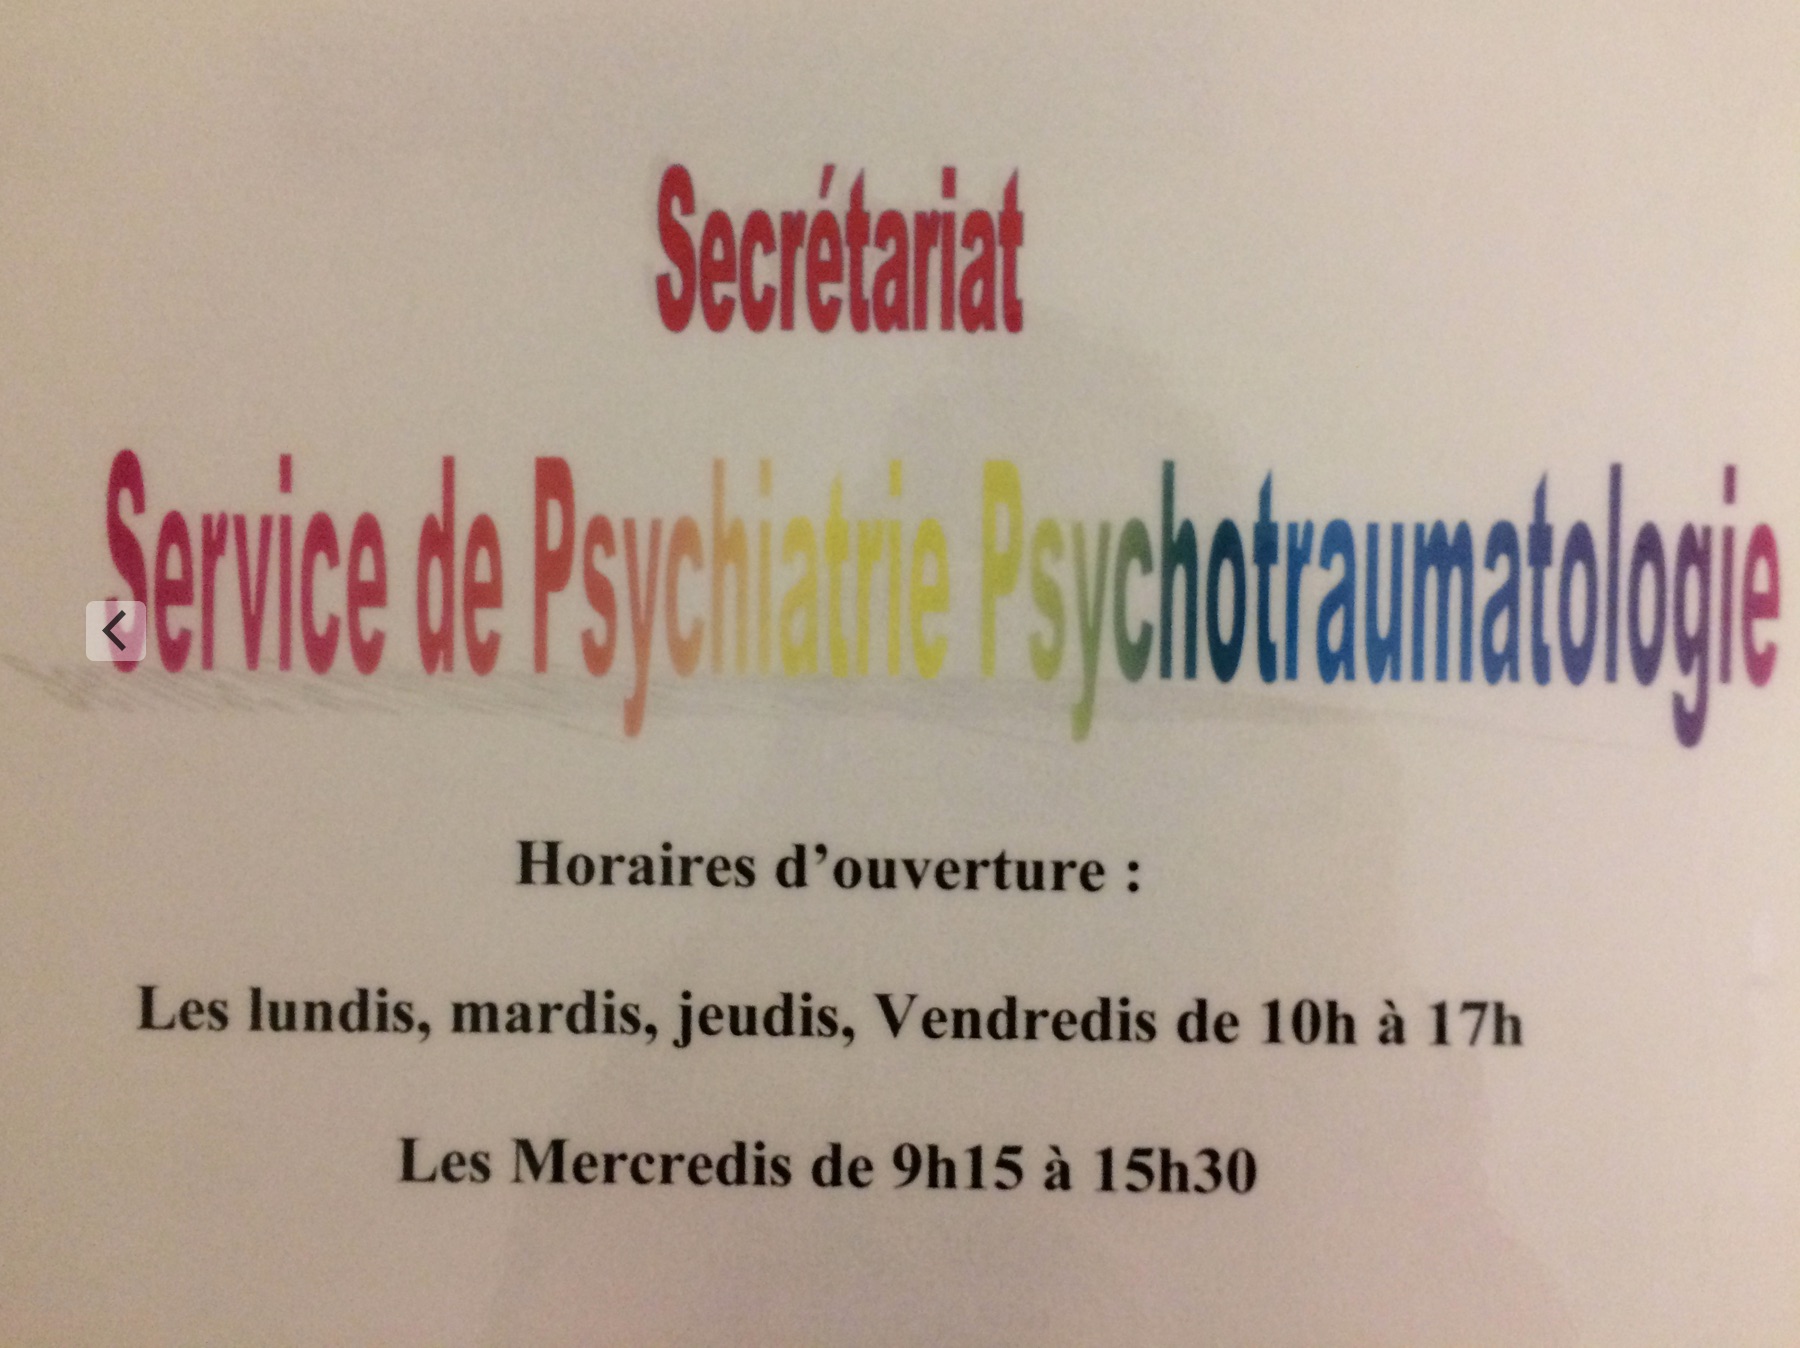

PS : la photo, c’est celle du valeureux Eric T, merci Eric ! Vous pouvez le suivre sur Twitter.

PPS : Un fidèle lecteur me fait remarquer que, le problème de ce macaron, c’est la durée !